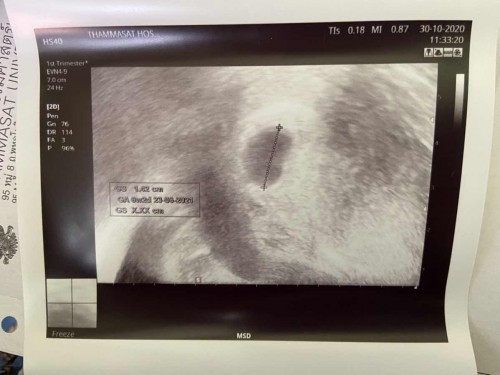

ตอนนี้ไปหาหมอเรียบร้อยแล้วค่ะ มีมูกเลือดออกมา คุณหมออัลตร้าซาวเจอแต่ถุงตั้งครรภ์แต่ไม่เจอลูก หมอนัดอีกสองสัปดาห์ กังวลใจมากเลยค่ะ อยากจะทราบว่าแม่ๆเจอลูกกี่สัปดาห์กันบ้างคะ มีภาวะเสี่ยงแท้งคุกคามด้วยค่ะ

อ่านเพิ่มเติมเจอตอน8สัปดาห์ค่ะ